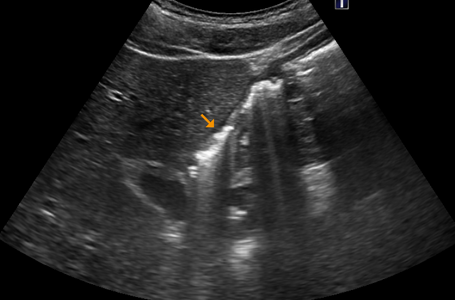

十二指腸潰瘍とは、十二指腸の粘膜に炎症が起きて、深い傷(潰瘍)ができている状態を指します。

• 超音波検査